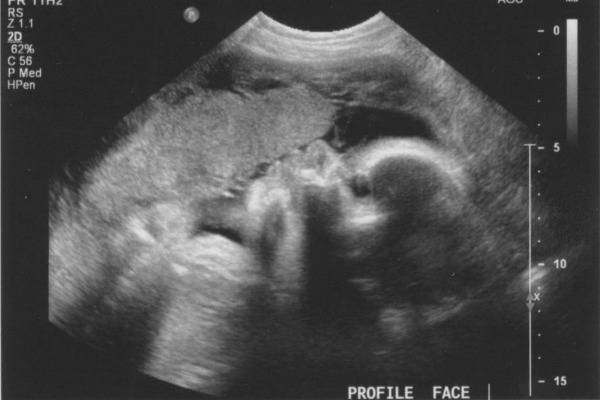

По согласованию с диагностом на второе УЗИ можно взять с собой и отца будущего ребенка. На мониторе сканера его ждет нечто довольно интересное, ведь теперь плод хорошо виден, можно полюбоваться его профилем, увидеть ручки и ножки, пальчики, нос, рот, глазницы, половые органы. Если УЗИ делается в 3D-формате, то будущие родители даже смогут увидеть, на кого больше похож карапуз.

- лицевой череп (глазницы, носовая кость, носогубный треугольник). Уменьшение размеров носовой кости характерно для синдрома Дауна. Перерывы сигнала в зоне носогубного треугольника указывают на расщелины губы и нёба;

Лицевой отдел осматривают на наличие дефектов развития глазницы, оценивают область носогубного треугольника.